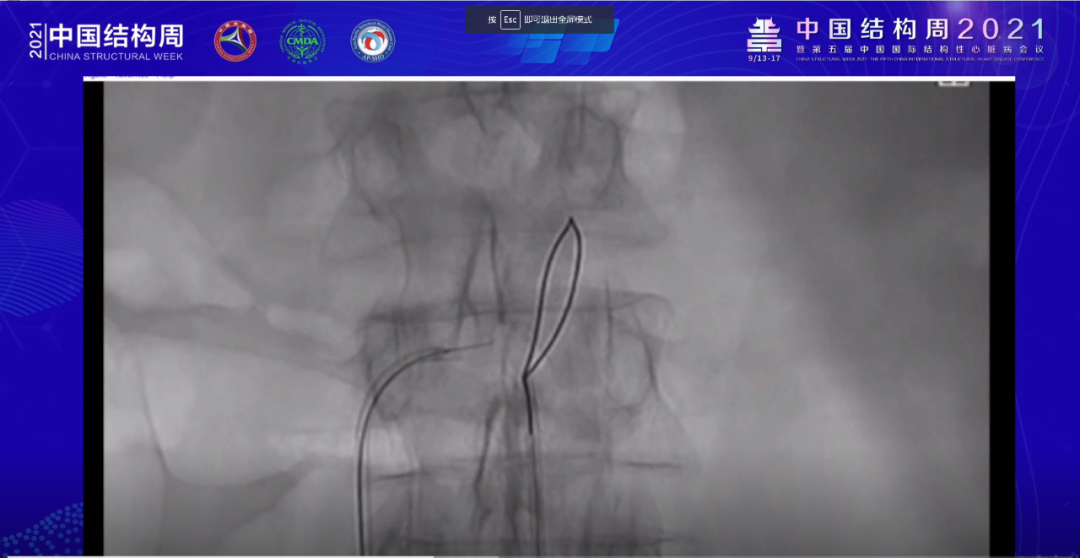

Adam Greenbaum教授带来的经腔静脉入路TAVR手术则是国内临床上较为罕见的一类入路方式。潘文志教授也表示,国内大多数TAVR术者对经腔静脉入路的认知大多来源于文献,真实世界中如何进行手术操作,整体手术流程及操手术过程中需要注意哪些事项还不得而知。

本次Adam Greenbaum教授的手术录播病例则十分详尽,整个演示过程几乎是点对点,step by step地进行了细致展示。

首先是穿刺点的位置——肾动脉下方2cm左右,且需要结合术前CT扫描准确判断。同时穿刺时还需要采用圈套器放置于腹主动脉穿刺点附近,为之后的操作建立基础。

随后,在股动脉留置可调弯穿刺鞘,导丝连接电刀,使得导丝更容易从下腔静脉穿过腹主动脉。待导丝完全从下腔静脉穿过腹主动脉,建立工作路径后,再在此基础上,置入一根6F导管,通过此导管植入超硬导丝,后植入输送鞘管,之后便可以依据人工瓣膜系统进行瓣膜置换操作。

最后,在止血步骤中,Adam Greenbaum教授也是通过输送鞘植入PDA封堵器进行封堵,后行造影复查封堵器效果,显示封堵完全,无残余分流。